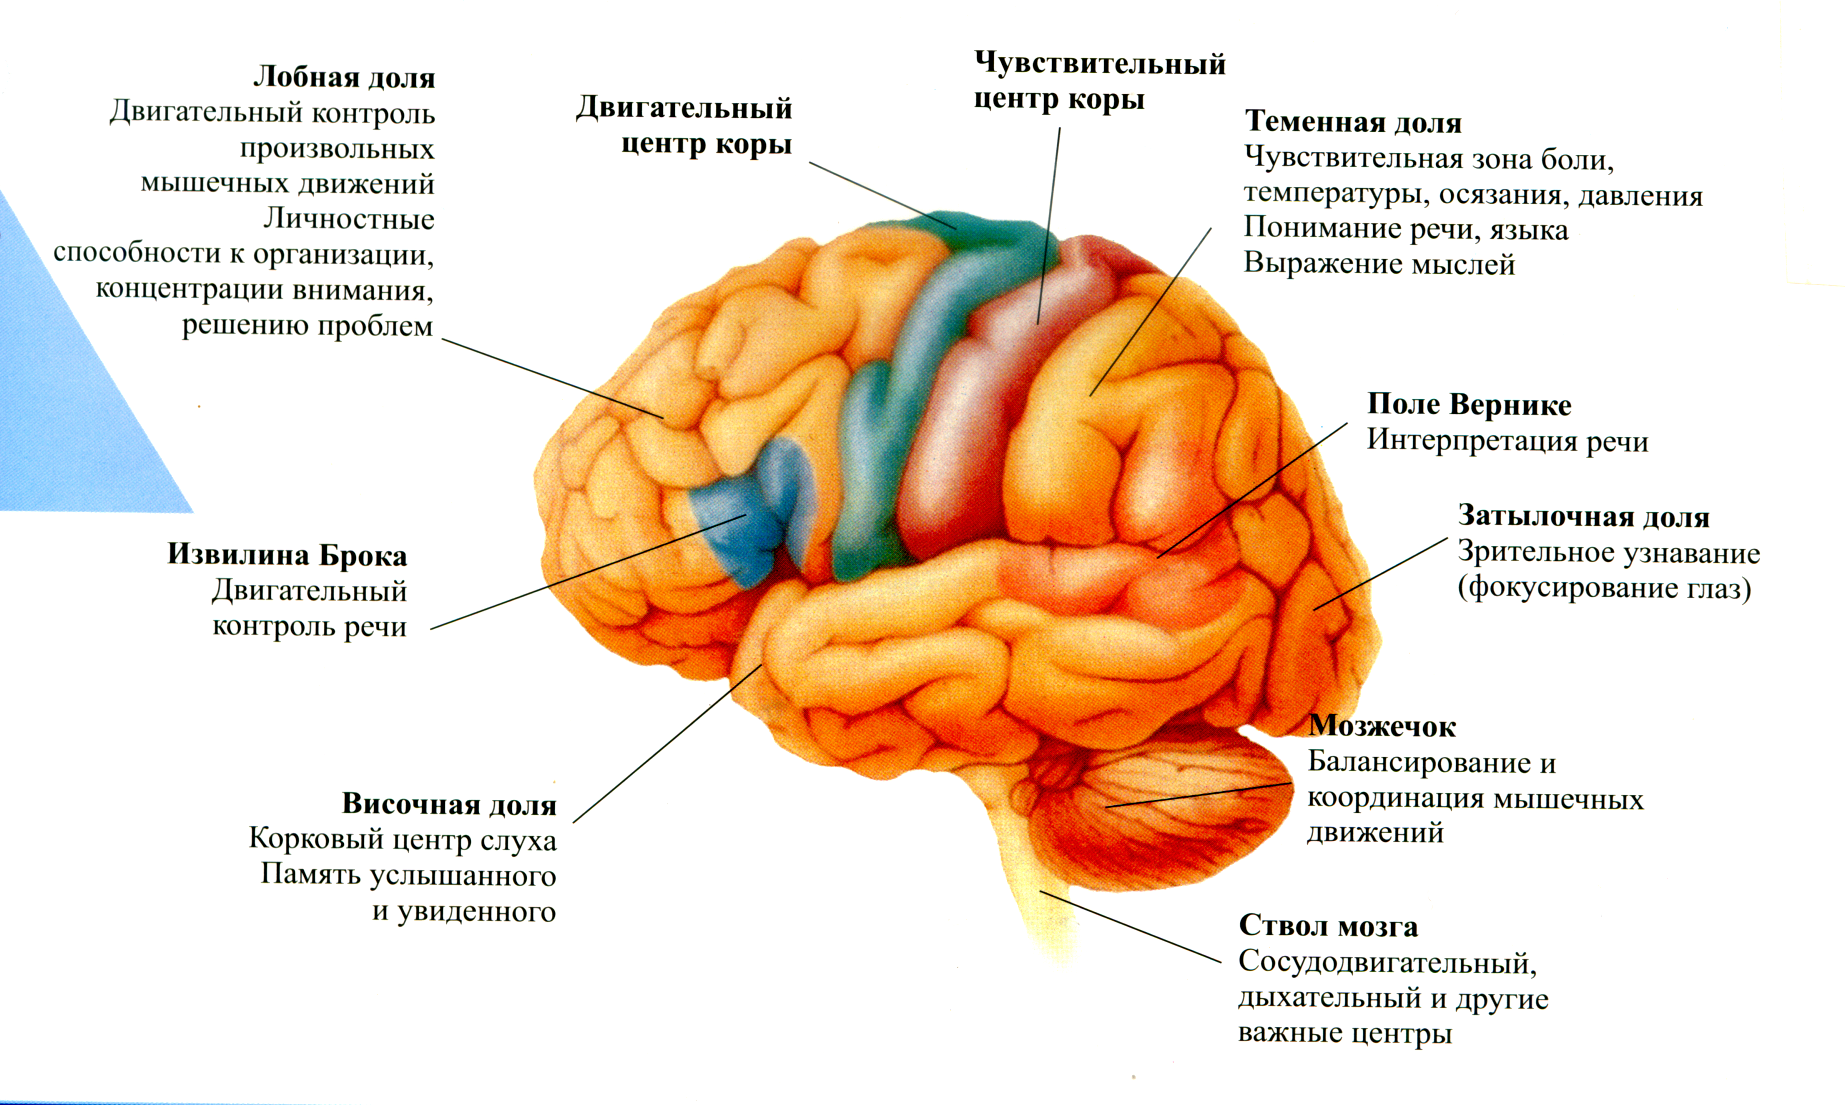

Физиология памяти: Механизмы и исследования